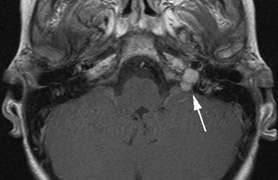

CNS hemangiomas are the most common tumor of VHL, affecting 60% to 80%, with a predilection for the cerebellum and spinal chord. An enlarging cystic component is a frequent finding in symptomatic tumors. Patients typically present in their early 30s; headaches or neck pain in affected individuals should not be ignored.172,173 On microscopy, CNS hemangiomas resemble retinal capillary hemangiomas. Their malignant potential is low.174 The treatment is surgical (Fig. 17, A and B).13

Fig. 17. Images from a 13-year-old boy with Von Hippel-Lindau syndrome. (a) Coronal postcontrast T1-weighted imaging reveals a cystic lesion with an enhancing nodule at the pial surface typical of a hemangioblastoma. (b) A second solid enhancing hemangioblastoma is seen at the craniocervial junction on a sagittal postcontrast T1-weighted image. (c) Associated cystic lesions (arrows) are seen within the pancreas.

Pancreatic lesions may be nonsecretory (most commonly cysts or cystadenomas) or secretory (islet cell tumor).179 In one study of 52 patients, 56% (29 patients) were found to have pancreatic lesions. The majority (19 of 29) had cystic changes only (Fig. 17C). Pancreatic lesions were the only abdominal manifestation of disease in 6 of 52 patients.180 In a separate study, pancreatic cysts did not show significant progression on follow-up examinations over an average period of 5 years.181 Like pancreatic cysts, islet cell tumors appear to be frequently asymptomatic.182